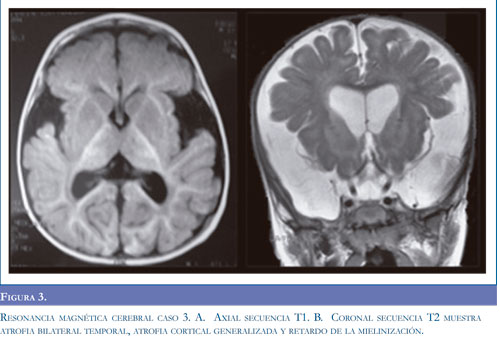

Neuroinfección, la cual se descartó por análisis de líquido cefalorraquídeo, se inició manejo anticonvulsivante con fenitoína y fenobarbital ante la sospecha de crisis epiléptica; sin obtener mejoría. Presentó síntomas respiratorios, con radiografía de tórax que mostró opacidad alveolar derecha y hemograma con aumento de leucocitos a expensas de neutrófilos, por lo cual se inició tratamiento antibiótico. Se remitió a Hospital de III nivel para manejo especializado. Al examen neurológico se encontró alerta, irritable, con sialorrea, nistagmus horizontal, hipertonía generalizada, hiperextensión de extremidades y cabeza, hiperreflexia con clonus aquiliano bilateral, respuesta plantar extensora bilateral, movimientos distónicos, y pérdida de las habilidades motoras previamente alcanzadas. Se realizó electroencefalograma sin evidencia de actividad paroxística epileptiforme, y se suspendieron los anticonvulsivantes. Las imágenes de tomografía axial computadorizada de cráneo (TC) evidenciaron atrofia bilateral de lóbulo temporal (Figura 1A). Con impresión diagnóstica de encefalopatía con disquinesia de probable origen metabólico se inició manejo con diazepam para control de crisis distónicas. Se realizó resonancia magnética (RM) cerebral evidenciando hipoplasia fronto-temporal, con aumento del tamaño de las cisuras silvianas, retardo en la mielinización y alteración de la señal en ganglios basales (Figura 2).

Caso 2. Femenina 3 años de edad, hermana del paciente anterior, con antecedente de retardo global del desarrollo, sin que hubiera adquirido marcha independiente. Al examen físico, estaba alerta, con pobre relación con el medio, sialorrea persistente, lenguaje con monosílabos, aumento del tono en las 4 extremidades, hiperreflexia generalizada, marchaba con apoyo en puntas de pies, incoordinación motora y posturas distónicas asociadas. Las imágenes de TC reportaron atrofia temporal bilateral, con amplitud de la cisura de Silvio (Figura 1 B). Las imágenes de resonancia magnética cerebral mostraron hipoplasia fronto-temporal con aumento de la cisura silviana y compromiso ganglio basal (Figuras 2 C-D). La determinación de ácidos orgánicos de cadena corta y media confirmó el diagnóstico de aciduria glutárica tipo I (Tabla 1). Se inició manejo nutricional con restricción proteica libre de lisina y baja en triptófano, suplementación con L-carnitina y benzodiacepina para el manejo de las distonías. Cuatro meses después continúa manejo nutricional y farmacológico, controles ambulatorios y terapia integral, evidenciando mejor relación con el entorno, mejoría en lenguaje expresivo y asistencia al jardín infantil.

La sospecha clínica fue apoyada en todos los pacientes con imágenes típicas de atrofia frontotem-poral bilateral conocidas como "alas de murciélago" en la tomografía axial computadorizada y por alteraciones de la sustancia blanca en grados variables en la resonancia magnética cerebral como se describe en la literatura (11).